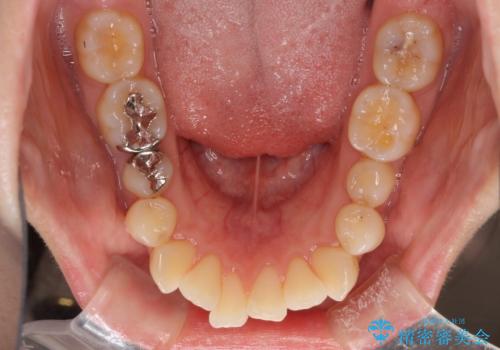

- 口元の閉じにくさと、前歯のでこぼこの歯並びを気にして来院された患者様です。

口元を積極的に引っ込めるために、上下左右の小臼歯計4本を抜歯することとしました。

セオリーでは第一小臼歯を抜歯しますが、上下右側は第二小臼歯に銀歯が装着されているため、第二小臼歯を抜歯することとしました。